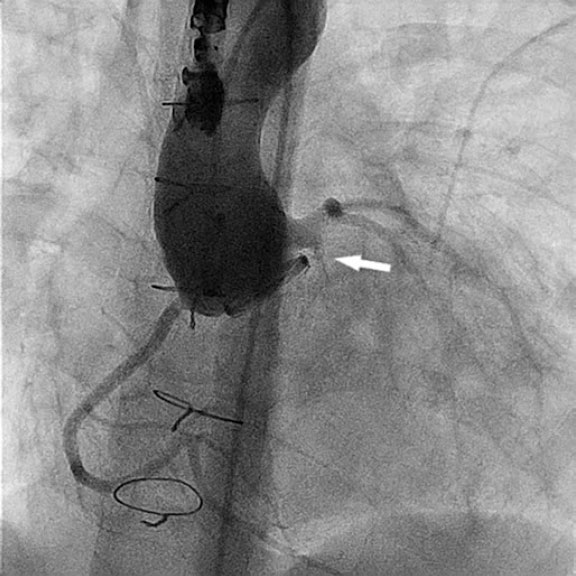

We catheterized the fistulous tract using a modified 4-Fr NIH catheter (Cordis, United States) and a 0.035 in hydrophilic guidewire. Afterwards, we mounted a 4-Fr delivery catheter over the guidewire, and deployed a 4 mm × 4-mm Nit-Occlud PDA device (PFM Medical, Germany) (figure 2 and video S2). We chose this device over nitinol mesh occluders because their greater length and retention discs were considered at risk of interfering with the coronary artery.

Figure 2.